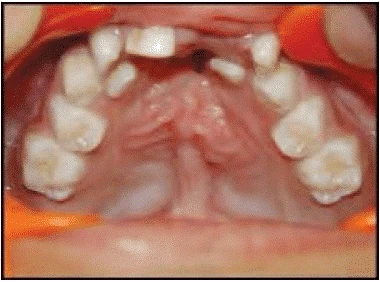

Khẩu cái

Kiểm tra niêm mạc khẩu cái nhằm:

a. Khẩu cái sưng bệnh lý: có thể là dấu hiệu của mầm răng ngầm, nang, v.v…

b. Cắn sâu có thể gây chấn thương đến vết lõm trên khẩu cái hoặc vết loét niêm mạc.

c. Khẩu cái sâu và có hình dạng khác nhau tương ứng với hình dạng khuôn mặt, chẳng hạn như bệnh nhân có khuôn mặt brachy thì khẩu cái thường rộng và nông hơn so với bệnh nhân có khuôn mặt dolico.

d. Sự hiện diện của khe hở vòm miệng với nhiều mức độ khác nhau. Sẹo do phẫu thuật khẩu cái có thể ảnh hưởng đến sự phát triển bình thường của xương hàm trên.

- Hình dạng và sự đối xứng của cung răng trên và cung răng dưới.